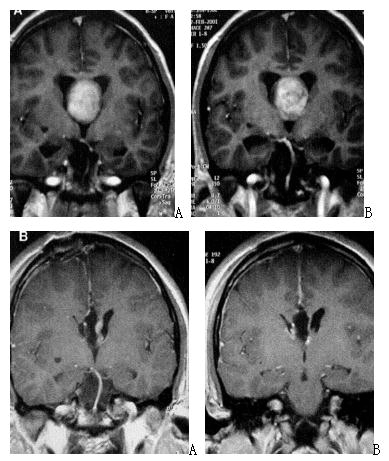

2. 脊索瘤

目前,绝大多脊索瘤首选内镜经鼻手术治疗。

图2. A、B手术前增强磁共振,提示复发巨大全斜坡脊索瘤;C、D内镜经鼻手术后增强磁共振,提示肿瘤全切。